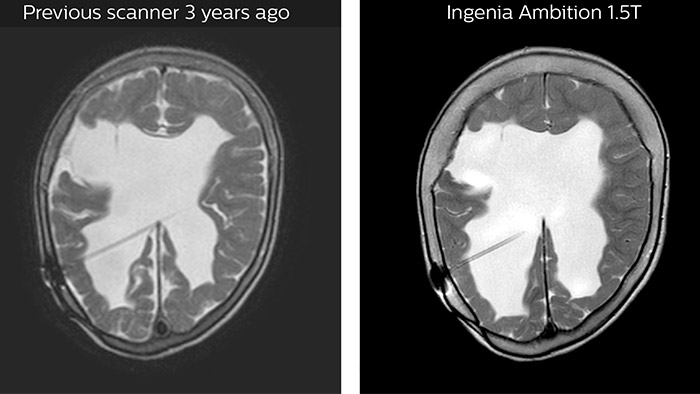

The MRI staff at Altona Children’s Hospital always make sure there is enough time available to adequately scan each patient. “Throughput is not our priority, we take the time we need for every patient,” says Dr. Junge. “Essential to us are the quality and resolution of the images, for every sequence. Ambition helps us achieve our primary goal of obtaining excellent quality images with high resolution – there is a world of difference with our old system.”

A leap in image quality thanks to progress in technology

“It was also a very pleasant surprise to us that we could get excellent resolution on other anatomies, as well, such as the spine, head, and knees, that we didn’t see previously. That is something that helps us tremendously as anatomy of children can be very small.”

Hydrocephalus post hemorrhagic Both pictures show a ventriculoperitoneal shunt. With our previous scanner our hydrocephalus protocol needed about 25 min. With Ambition the examination time is about 14 min. including a CSF PCA sequence to show flow in the aqueduct.